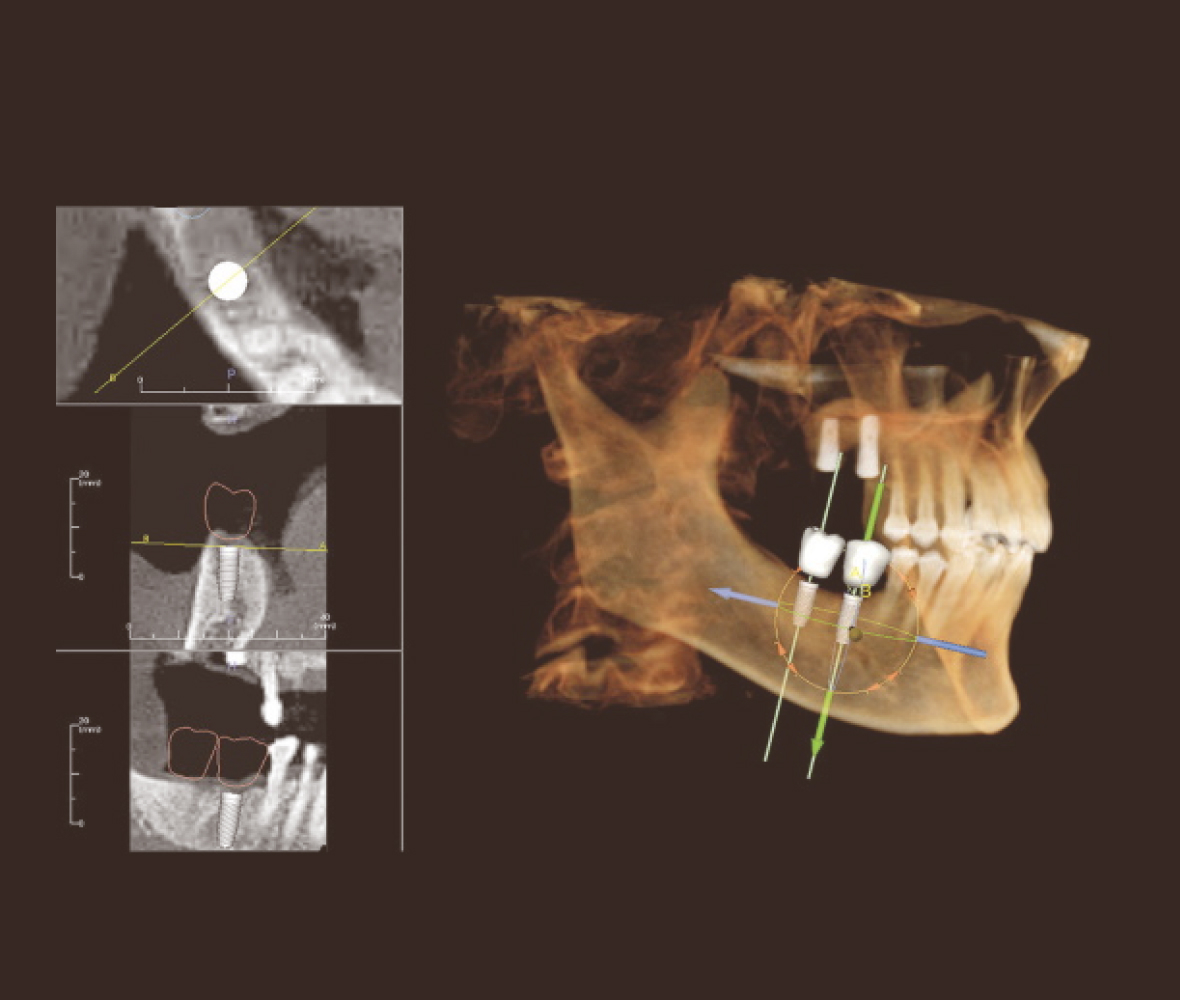

インプラント治療は、歯を失った部分にチタン製の人工歯根を埋め込み、その上に人工の歯を装着することで、見た目と噛む力を取り戻す治療です。

当院では、丁寧な問診とCT撮影を通じて骨の状態などを精密に確認し、患者さまのお口にインプラントが合うか判断した上で治療しています。